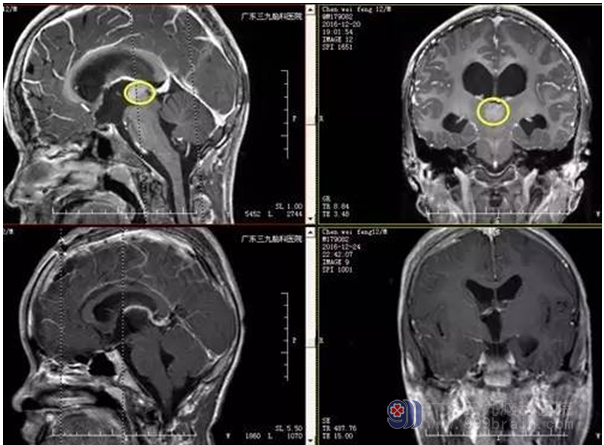

术前MR和术后MR对比显示肿瘤全切

CT平扫肿瘤实质多为高密度,与生殖细胞瘤细胞密集有关,少部分肿瘤内低密度区可能与肿瘤生长迅速,发生坏死、囊变或可能因含其它组织成分有关,本例患者CT见稍高密度影,未有囊变、坏死出现。MR平扫T1WI多为均匀等信号或略低信号,信号不均与坏死、囊变有关。T2WI多为高信号。增强呈明显强化,少数为不均匀强化。本例MR呈稍长T1稍长T2信号影,范围约1.83cm*1.56cm*1.59cm,增强后呈明显强化。